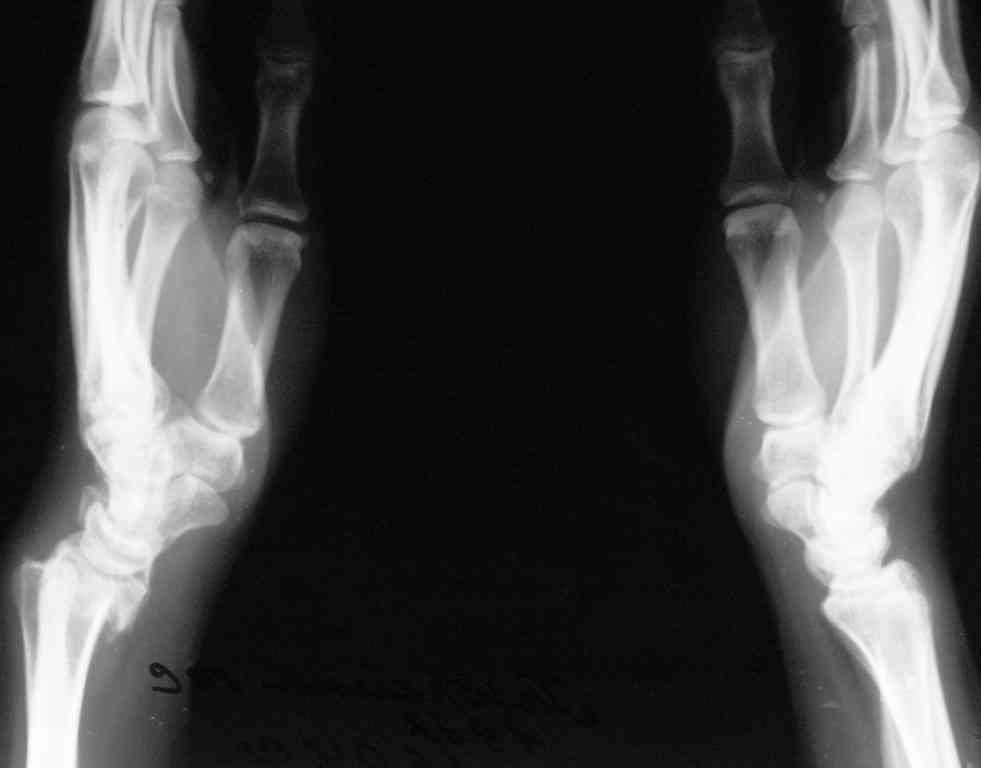

Спице-стержневой аппарат с компактотомией лучевой кости, костная пластика локтевой с удалением пластины. Не комфортно, но больше шансов на благоприятный исход. Заканчиваю лечение с похожей деформацией лучевой кости.